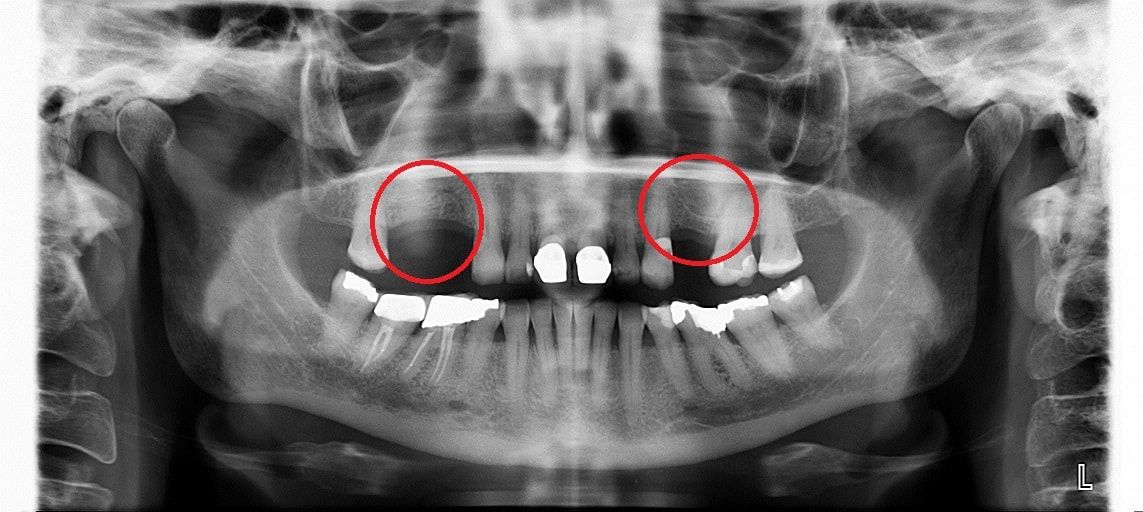

• до синус-лифтинга

• после синус-лифтинга

• после установки имплантатов в верхнюю челюсть

• коронки установленные на имплантаты